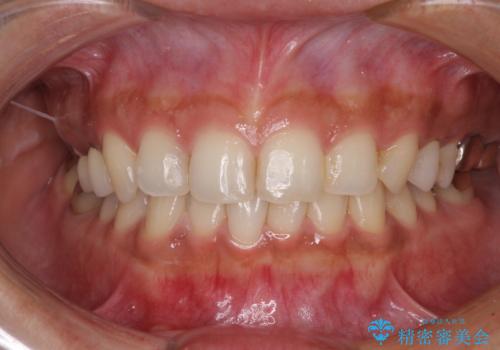

- 冷たいものがしみたり、ものが挟まったり、噛んだときに痛んだりするとのことで来院された患者様です。

治療開始時は右上奥歯と前歯のみが気になっていたのですが、その後下顎左右の奥歯に強い痛みや銀歯の脱離などが頻発し、問題のあるところは全て治療を行うこととしました。